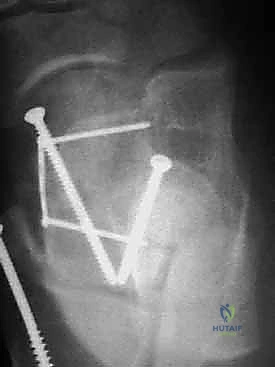

المرحلة الرابعة: التثبيت الداخلي (Internal Fixation)

بمجرد التأكد من أن العظم عاد لشكله الطبيعي تماماً، يتم استبدال الأسلاك المؤقتة بتثبيت دائم. يستخدم الدكتور هطيف أحدث الغرسات الطبية العالمية:

* مسامير التيتانيوم المجوفة (Cannulated Screws): مسامير قوية جداً يتم إدخالها عبر العظم لضغط أجزاء الكسر معاً.

* المسامير بدون رأس (Headless Compression Screws): تُستخدم في المناطق المغطاة بالغضروف، حيث تُدفن بالكامل داخل العظم لكي لا تحتك بالمفصل وتسبب تآكلاً.

* الشرائح المعدنية الدقيقة (Mini-Plates): تُستخدم أحياناً لتدعيم التثبيت في حالات التفتت الشديد (Comminution) حيث لا تكفي المسامير وحدها.

يتم وضع المسامير عادة من اتجاهين (من الأمام للخلف، ومن الخلف للأمام) لإنشاء هيكل ميكانيكي صلب يتحمل الضغوط.

المرحلة الخامسة: التحقق الإشعاعي الفوري والإغلاق

قبل إنهاء العملية، يستخدم الدكتور هطيف جهاز الأشعة السينية المتحرك داخل غرفة العمليات (C-arm Fluoroscopy) لأخذ صور متعددة والتأكد من:

1. المحاذاة المثالية للكسر.

2. عدم وجود أي فجوات أو درجات في السطح المفصلي.

3. الطول والموقع الصحيح للمسامير (للتأكد من أنها لا تخترق المفاصل المجاورة).